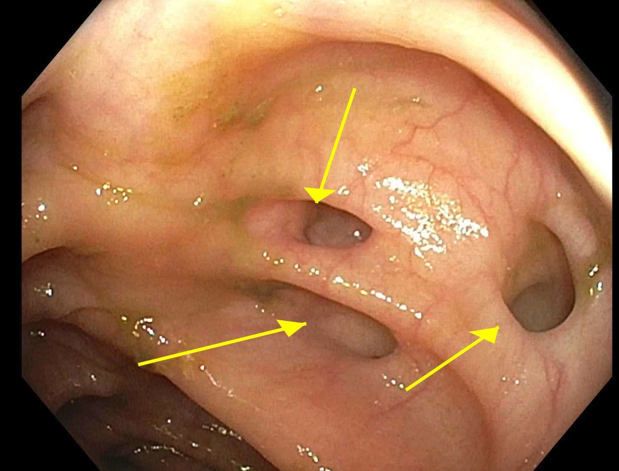

- Frequently is an incidental finding during colonoscopy

- Symptomatic patients, classic presenting symptoms and confirmation with radiology or via colonoscopy (Mayo Clin Proc 2016;91:1094)

- Colonoscopy or Xray following barium enema (StatPearls: Diverticulosis [Accessed 21 April 2022])

- Colonoscopy should be avoided in acute diverticulitis (Mayo Clin Proc 2016;91:1094)

Clinical images